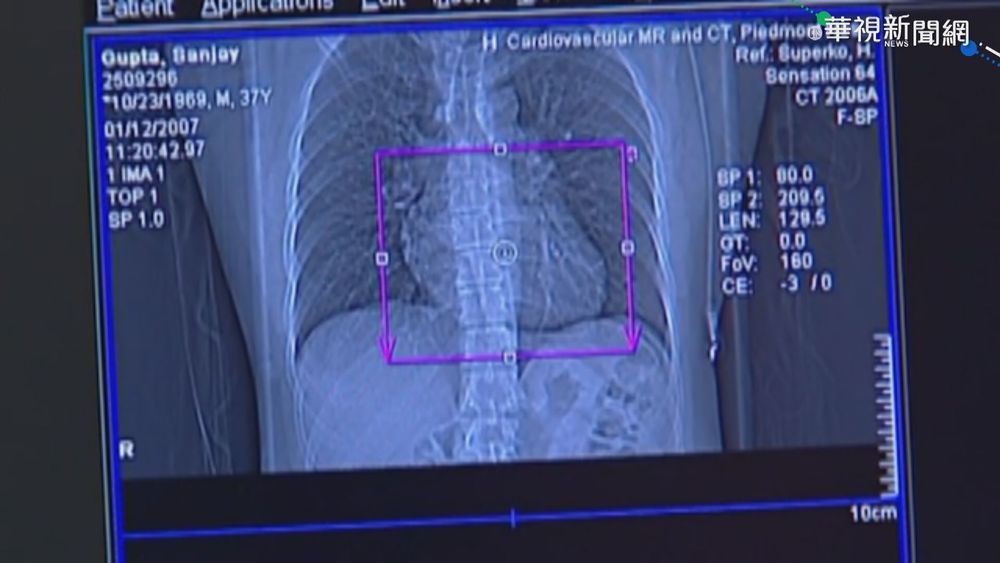

美:輝瑞.莫德納 恐與罕見心臟發炎有關

牙周病害心臟發炎 男腦中風亡!